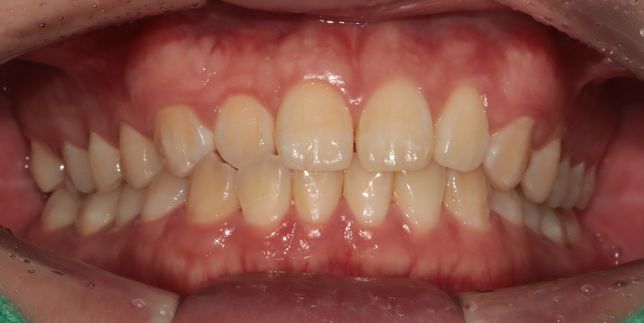

- 생활꿀팁생활Q. 양악 vs 비발치 교정 vs 아무것도 안하기여기에 글 몇번올렸는데 이제 고민그만할려고 마지막으로 올리는거예요ㅠㅠ옆모습이 하악턱과 입이 튀어나와보여 컴플렉스 인 남성입니다 다른사람이 보기에는 어떨지는 모르겠습니다그런데 미용적으로 개선하고싶으나 양악하기에는 부작용도 무섭고 수술도 무서워요 죽을수도 있다고 들어서요...그래서 고민하는게1번 양악-가장드라마틱하게 턱도줄이고 입툭튀도 줄일수있을것같긴해요2번 -발치교정하기에 치열이 아까운것같아 사랑니쪽으로 전체이동 비발치교정 하기-이러면 입툭튀 조금은들어간다고 들었어요 대신 입이들어가서 턱이 조금나와볼일수있다는데 치아 들어가도 2~3mm라 별차이 없을수도 있다고들어서...맞는지는 모르겠습니다(현재 사랑니4개 없는상태입니다)3번 - 그냥 건강하게 살기인데 미용은 주관적인거라누가보느냐에따라 안모가 남성다워 보인다고 하기도하고 턱이랑 입이 좀 나온것같다 오리입술같다 그러기도 해서 결정장애왔습니다전문의가 평가하기에 1,2,3번중 어느게 맞을까요?그외 의견도 상관없습니다선택한이유도 알고싶습니다개인적인거니깐 정답이 아나라는것은 알고있습니다사진은 왼쪽이 현재 오른쪽이 양악 포토샾입니다그냥제가한거예요 참고사항ㅎ

- 치과의료상담Q. 제 옆모습을 가끔 보면 턱이랑 입이 나온것같아보이는데 전문의가 평가하기에도 그런지 알고싶어요질문1. 제 옆모습을 가끔 보면 턱이랑 입이 나온것같아보이는데 전문의가 평가하기에도 그런지 알고싶어요가끔 사진찍히거나 거울볼때 옆모습이 입이랑 턱이 남들보다 나온것같다는 생각이들거든요 이런게 주걱턱인가? 이게 치과에 문의하는게 맞는지 모르겠지만 전문의님 개인평가를 듣고싶어요~ 나중에 구강악쪽 양악수술 상담한번 받아보려고요질문2. 만약 입만 넣는다면 발치없이 인비절라인 같은 투명교정으로도 가능할까요?질문3. 제 앞니 치근이 짧나요?이미지가 포함된 질문이에요.

- 치과의료상담Q. 중안면부 꺼짐있는경우 양악을 하면 개선이 되나요?중안면부 꺼짐있는 경우 미용적인 목적으로 양악수술을 하면 개선이 되나요?보통은 이런경우 코수술을 하게되나요?치아 교합은 정상인데 일자목이라서 그런건지모르겠지만 옆모습을 봤을때 입체적이지 않고 약간 1자 모습? \\모양 이여서 콤플렉스입니다.오히려 이런경우 부작용이 크나요?자료가 부족하겠지만 그냥 의사님들 개인생각 적어주시면 도움이될것같습니다지인분들마다 평가하시는게 달라서 저스스로도 수술고민하는게 맞는지 잘모르겠습니다 (남자라서 괜찮다, 전혀모르겠다, 약간 턱이 나온것같다, 입이나온거다,연예인할것도 아닌데 왜그러냐 등등)그리고 제가 살짝 팔랑귀라서 고민하게되네요이미지가 포함된 질문이에요.

- 성형외과의료상담Q. 턱 돌출 성형 및 구강악 수술에대한 문의아하에 치과쪽에 질문을 자주애용해서 여기에 의사님들 개인적인 의견을 여쭙고자 질문남깁니다구강악외과에서 턱정밀상담 결과 하관평균길이가 성인남성평균보다 길고 돌출되었다고 들은 이후에 신경이 쓰여 수술 질문좀 하고싶습니다의사분께서는 기능적으로 이상은 없다고 수술을 권장하지는 않았습니다 미용적인거라고해서..아하 의사님들 개인적인 생각으로는 하관 수술하면 괜찮아질까요?그리고 돌출된 턱만 따로 수술가능한가요?수술이란게 기능개선이 주목적인데 저는 미용목적이니 괜히 할려고 고민하는게 아닌가 걱정되어서요양악수술이나 하관수술해서 괜히 후회할까봐서요실제와 사진은 다르겠지만 ct와사진만보고 개인적은 의견 적어주시면 참고하도록 하겠습니다댓글달아주시는 의사님들 감사합니다^^이미지가 포함된 질문이에요.